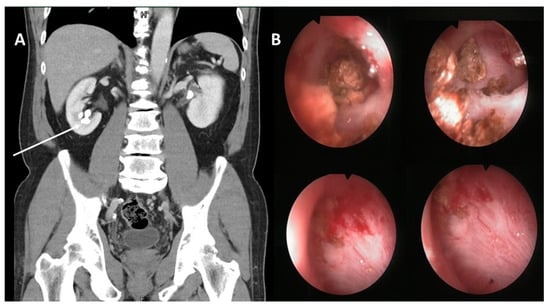

| Chang et al. (present study) | M/R/60 | Right heart | PNL (first-described) | Endovascular |